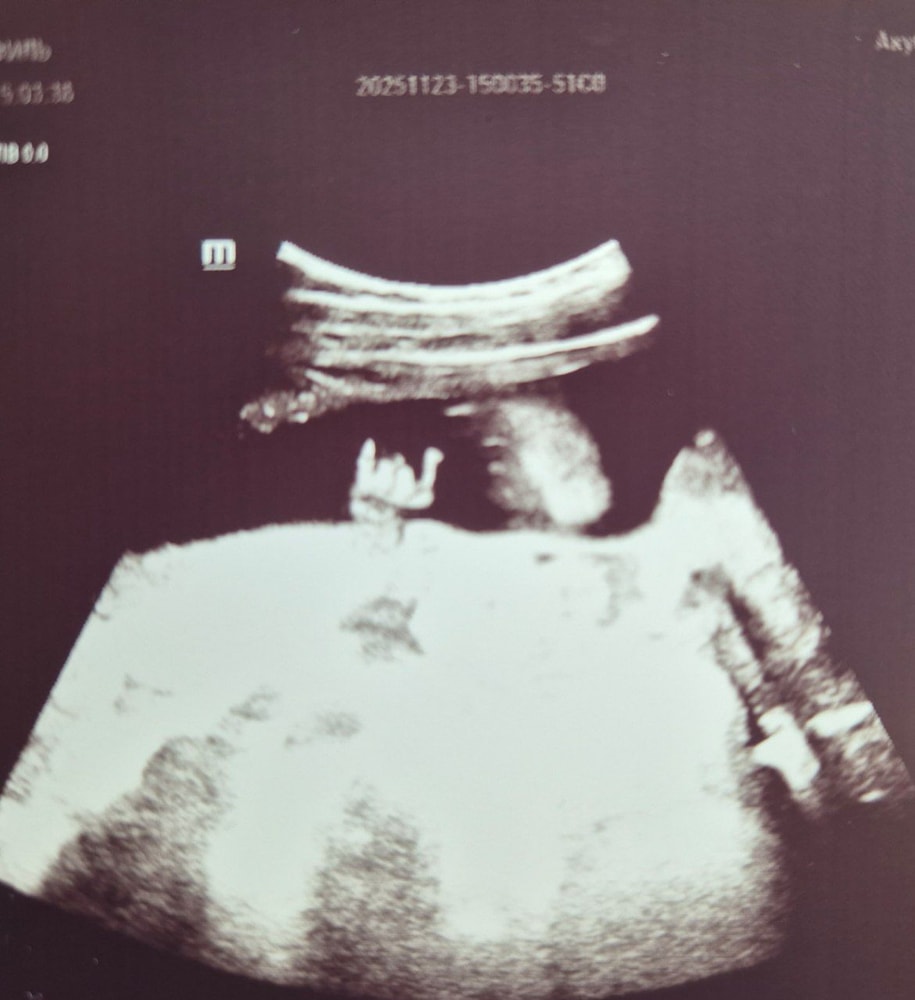

Первый скрининг💙

Вот мы и прошли первый волнительный рубеж- 1 скрининг 18.11.2025

🔥Итоги по сроку 12 недель по последнему УЗИ и 12+1 по ПДМ:

КТР: 60мм, что соответствует сроку 12+3

Обгоняем срок чуть-чуть)

С последнего узи 😁

Боже,это мне не кажется?Он «козу» показывает ручкой?🤣

Полина, даа, её самую.

Мама с папой в машине, походу, Князя переслушали🤣